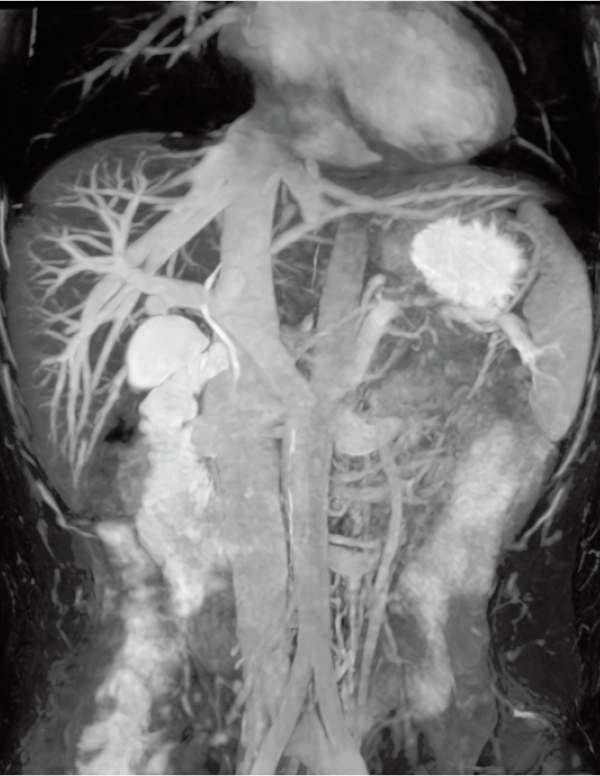

3D MRCPA (MIP)

Lower extremity

non-contrast MRA (MIP)